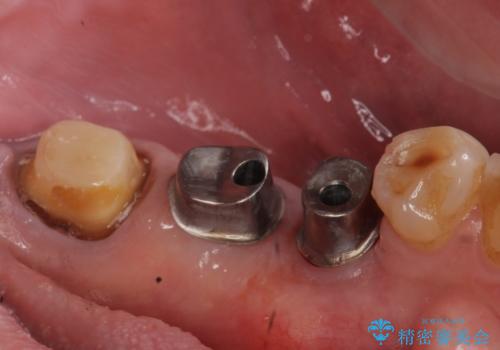

欠損部位である左下5、6番目にインプラントを埋入し、オールセラミッククラウンによる補綴を行いました。

当院では主にストローマンという種類のインプラントを治療に用いています。

ストローマンは世界的にもNo1のシェアを誇り、骨との適合にも優れたインプラントです。

カスタムアバットメントについて

カスタムアバットメントは患者様それぞれの歯茎に合わせて製作されたオーダーメイドのアバットメントです。

既製のアバットメントに比べ適合がよく、高い清掃性を誇ります。